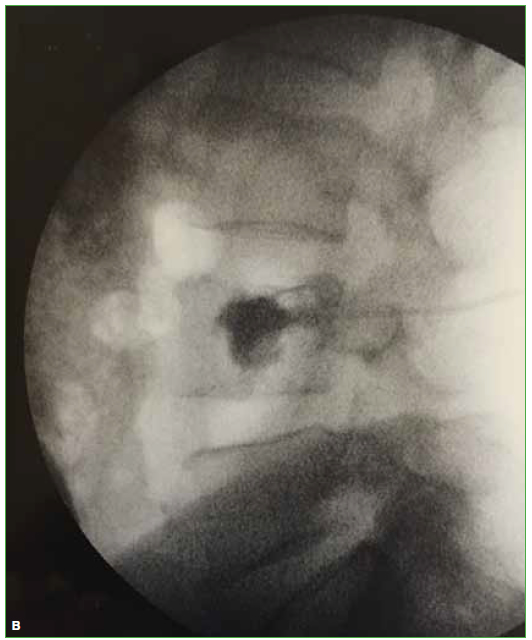

Las hernias discales intraesponjosas vertebrales o nódulos de Schmörl consisten en una herniación o una extrusión del núcleo pulposo del disco intervertebral a través del platillo vertebral hacia el cuerpo adyacente. Suelen asociarse a deformidades vertebrales, como la enfermedad de Scheuermann, o a enfermedades reumáticas, como la espondilitis anquilopoyética. En general, son hallazgos casuales y cuadros asintomáticos; son pocos los casos publicados de nódulos sintomáticos. Su aparición estaría relacionada con un platillo vertebral debilitado por traumatismo o estrés repetido. Cuando el nódulo es agudo o reciente, puede ser difícil diferenciar la degeneración benigna de una infiltración maligna o una infección. Presentamos un caso inusual de un nódulo de Schmörl doloroso en un hombre sin antecedentes de relevancia, que enmascaró una lesión metastásica de carcinoma pancreático a nivel lumbar. Se realiza una revisión bibliográfica. ABSTRACTIntraosseous disc herniation –or Schmörl nodes (SN)– are a herniation or prolapse of the nucleus pulposus of the intervertebral disc through the vertebral plate and into the adjacent vertebral body. They are usually associated with vertebral deformities, suchas Scheuermann’s disease, or rheumatic diseases, such as ankylopoietic spondylitis. In general, they are spontaneous and asymptomatic findings, and there are only a few reported cases of symptomatic nodes. The etiology is supposedly related to a weakened spinal plate due to trauma or repeated stress. When the node is acute or recent, it can be difficult to differentiate a benign degeneration from a malignant infiltration or infection. In this paper, we discuss the unusual case of a painful Schmörl node in a man with no relevant history and a masked metastatic lumbar spinal tumor originated from pancreatic cancer. We performed a literature review.Descargas